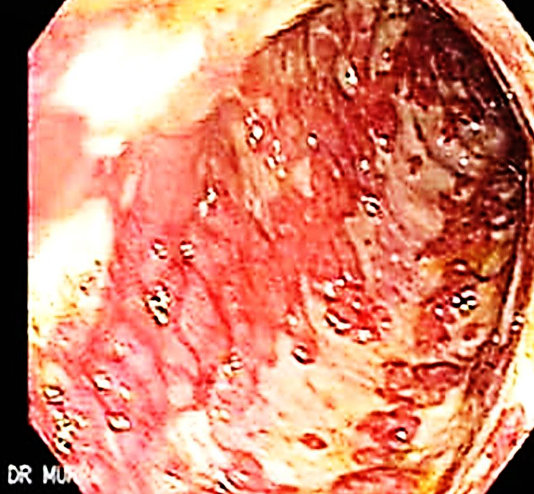

This is an endoscopic image of colon affected by ulcerative colitis. The mucosa is blotchy and broken in many places.

Q1: Name 3 common clinical symptoms of ulcerative colitis?

Lower abdominal pain, diarrhea, blood and mucus with the stool.

Q2: Name 2 features of a severe episode of UC?

Leukocytosis, increase frequency of the stool more than 6 times in the day, anemia. #Z

Q3: Name 2 ttt options for UC?

5-ASA, Corticosteroids. #Z Q4: Name 3 extracolonic manifestations of UC?

Arthritis, Ancylosing spondylitis, Uveitis, Episcleritis